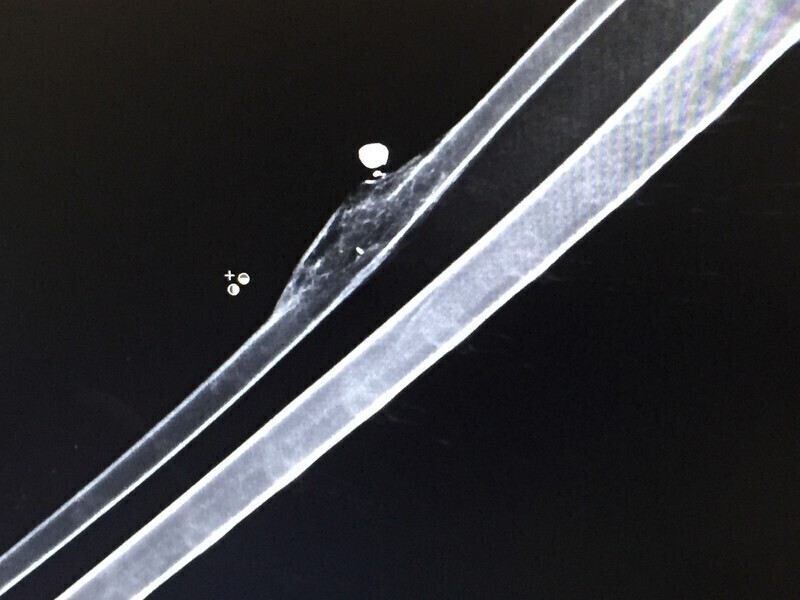

Wstępne badania rentgenowskie wykazało także ranę postrzałową w prawym skrzydle. - Widoczny śrut, moim zdaniem najprawdopodobniej z KBKS-u albo wiatrówki. Jest to sprawa dość stara, ponieważ wokół kości jest znaczny odczyn zapalny. Orzeł na pewno nie fruwał, bo nie pozwalały mu na to odniesione obrażenia. Na razie ciężko powiedzieć czy ptak będzie mógł wrócić do natury. Na pewno przez co najmniej miesiąc zostanie u Pawła Kowalskiego w ośrodku rehabilitacji dla dzikich zwierząt - dodaje Zbigniew Skrzek, lekarz weterynarii.